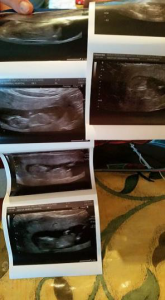

“This is a 3 month scan of a 32yrs old woman. 15 months ago she was told she had polysistic ovaries and would probably never conceive another child.

Her problems were so bad and she was so ill that her doctor recommended a hysterectomy. 7 months ago she started taking the minerals. Things started to improve and she felt better. Her scan proves she is 12 weeks 2 days pregnant after trying to get pregnant for 6 years.

She continues to take the sizzling minerals in fact she is taking 2 everyday along with the fizzy vitamins and she feels fantastic.

To say she and her family are over the moon would be an understatement indeed!”